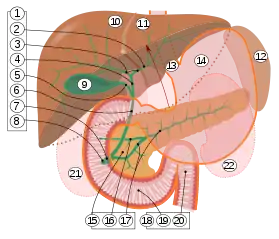

9. Gallbladder.

10–11. Right and left lobes of liver.

12. Spleen.

13. Esophagus.

14. Stomach.

15. Pancreas: 16. Accessory pancreatic duct, 17. Pancreatic duct.

18. Small intestine: 19. Duodenum, 20. Jejunum

21–22. Right and left kidneys.

The front border of the liver has been lifted up (brown arrow).[1]